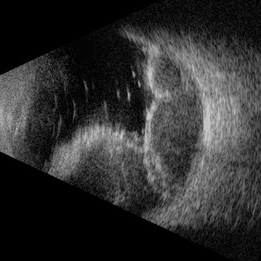

Suprachoroidal Hemorrhage

Nov 16 2019 by Sophia El Hamichi, MD

Ultrasound of the right eye of 43-year-old male presenting with suprachoroidal hemorrhage, note the multilobulated heterogenous echogenic mass aspect of the choroid

Photographer: Fiona J Ehlies, Murray Ocular Oncology and Retina, Miami

Condition/keywords: B scan ultrasound, suprachoroidal hemorrhage